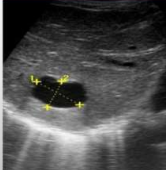

<p>¿Qué estudio es?</p>

¿Qué estudio es?

Ecografía